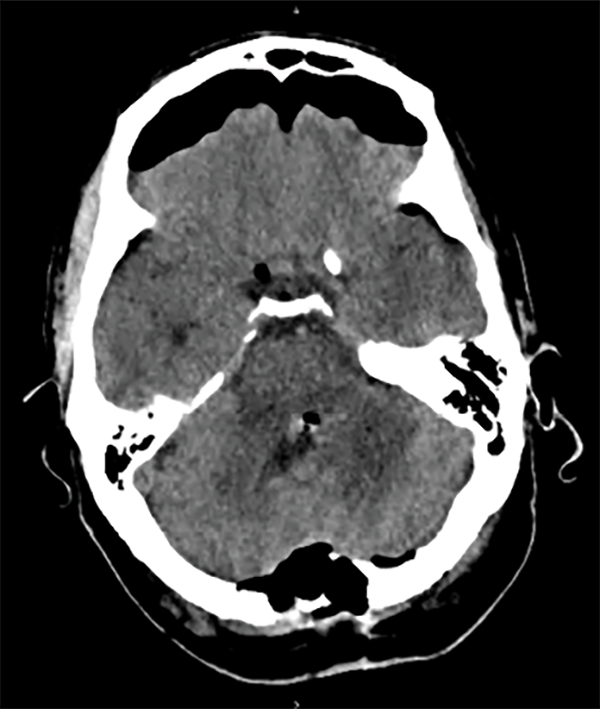

Basándonos en las características clínicas e imagenológicas disponibles la primera sospecha fue una lesión primaria de tronco de alto grado. Por la naturaleza focal de la lesión y su componente exofítico con proyección al piso del cuarto ventrículo se planteó un abordaje quirúrgico con el objetivo de obtener diagnóstico histológico, así como mejorar la sobrevida libre de progresión a través de una resección máxima segura. Dada la localización en proyección del cuarto ventrículo en su porción superior izquierda se optó por un abordaje telovelar con el paciente semisentado bajo monitoreo electrofisiológico intraoperatorio. En el intraoperatorio la poca diferenciación tumoral con respecto al tejido normal no permitió la exéresis completa. Se realizó tomografía de control postoperatoria que no evidenció hemorragia o hidrocefalia asociada (Fig. 3). La anatomía patológica reveló linfoma no Hodgkin de células B con alto índice de proliferación.

Fig. 3. Tomografía de control postoperatoria.